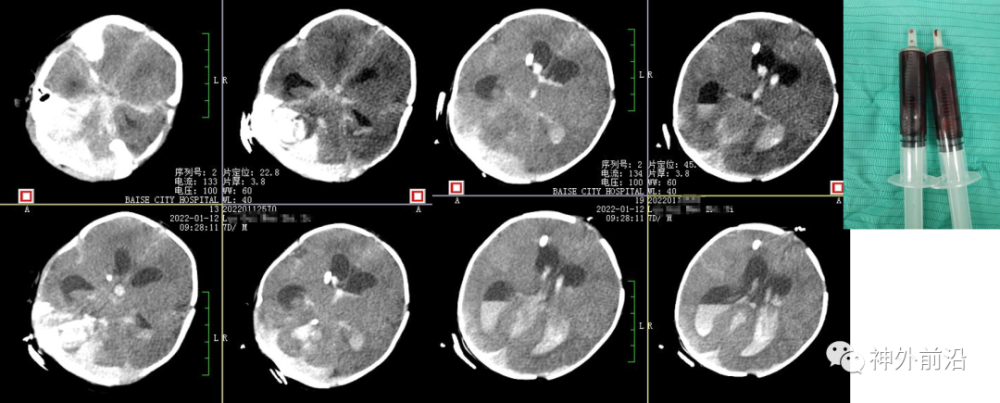

6.术后15小时复查CT,术中抽吸血肿

7.术后2天复查CT,血肿部分清除及退管

8.术后4天复查CT,血肿大部分清除及拔管